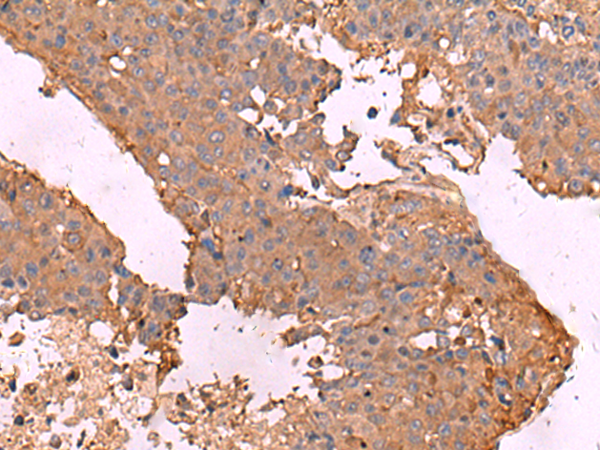

分类: 科研抗体货号: P04967别名: GPAPP; IMP 3; IMP-3; IMPA3应用: IHC反应种属: Human, Mouse, Rat